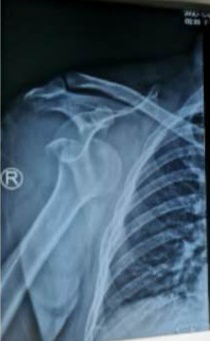

近日,一位现役军人,工作时不慎摔伤致右肩呈“方肩畸形”疼痛、活动受限,来到红会医院就诊。在得知患者身份情况后,急诊医学科手法复位室开通军人诊疗绿色通道,在急诊挂号、就诊、检查和收费等环节采取迅速便捷措施,并安排技术精湛的医生,10分钟内快速完成了肩关节复位术,得到了患者及家属的好评。